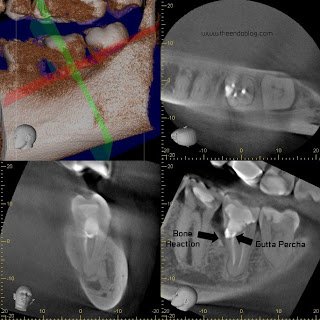

Root Canal on a C-shaped, 2nd molar, through a crown with mild angulation and calcified canals makes this root canal a “HIGH DIFFICULTY” level.  The clinician performing this treatment had challenges due to these issues.  Access was difficult, interpreting the c-shaped canal was difficult and C-shaped canal all led to the mesial perforation.  The calcified canals also made it difficult to instrument/fill to the apex.  The perforation was improperly managed by sealing with gutta percha and patient was not informed of the complication.